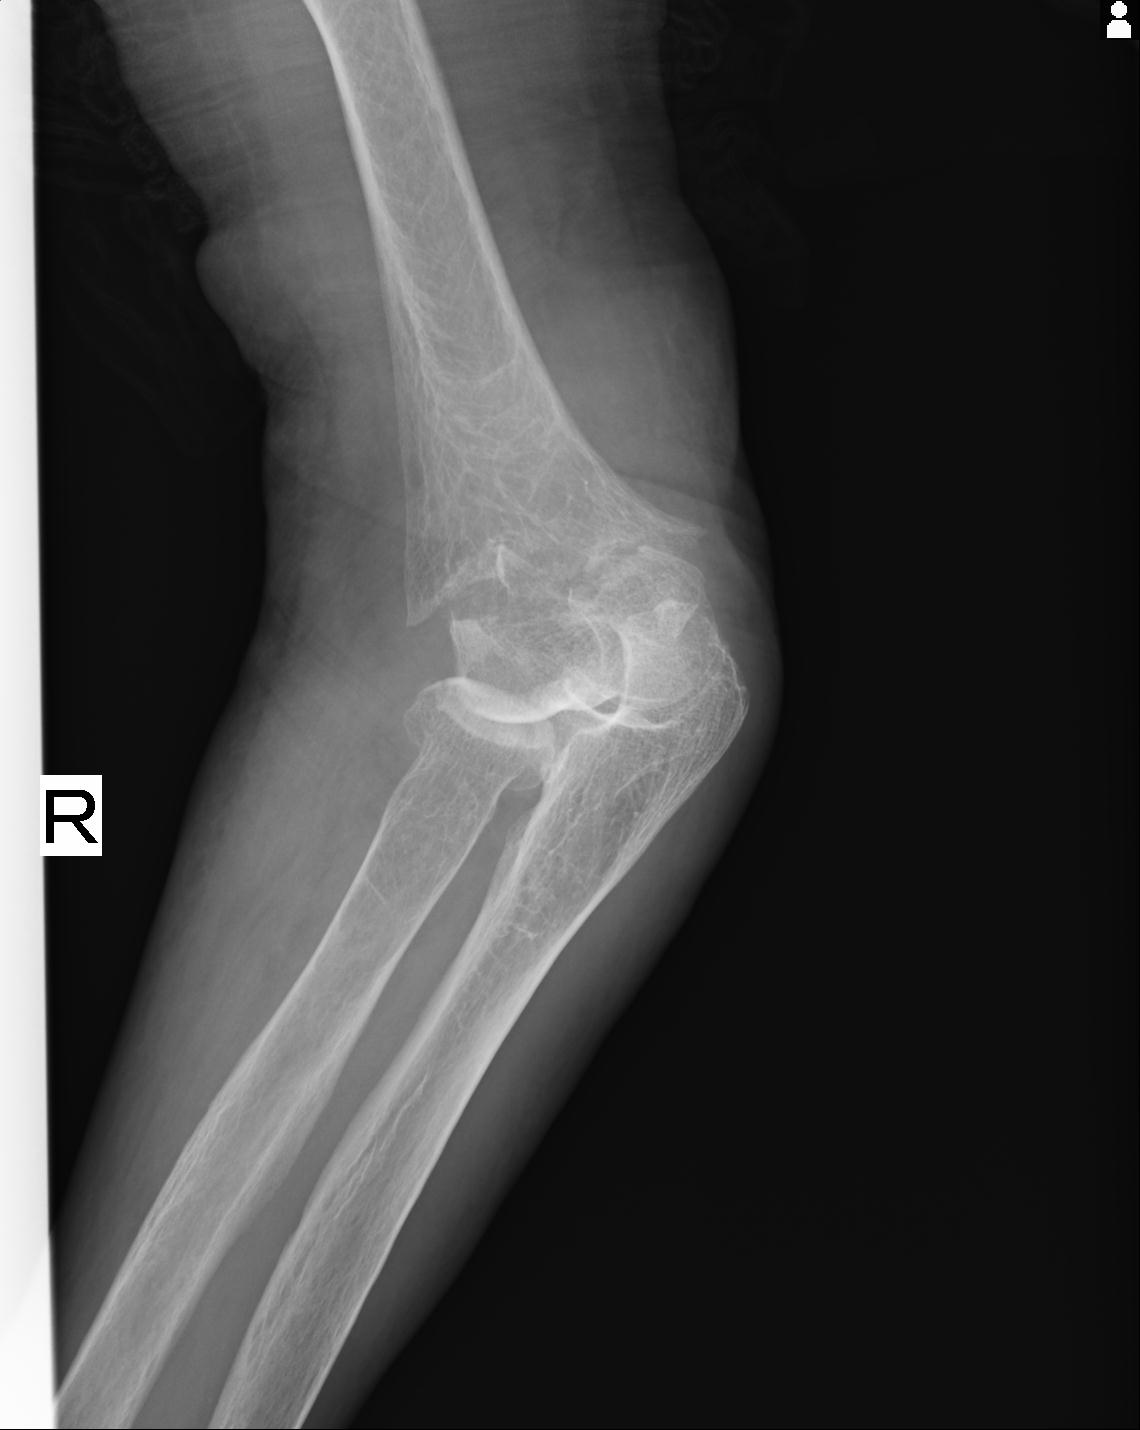

2271 1/25 右肘 4R 1/27 4R 3/24 4R 94歳女性 右通顆骨折